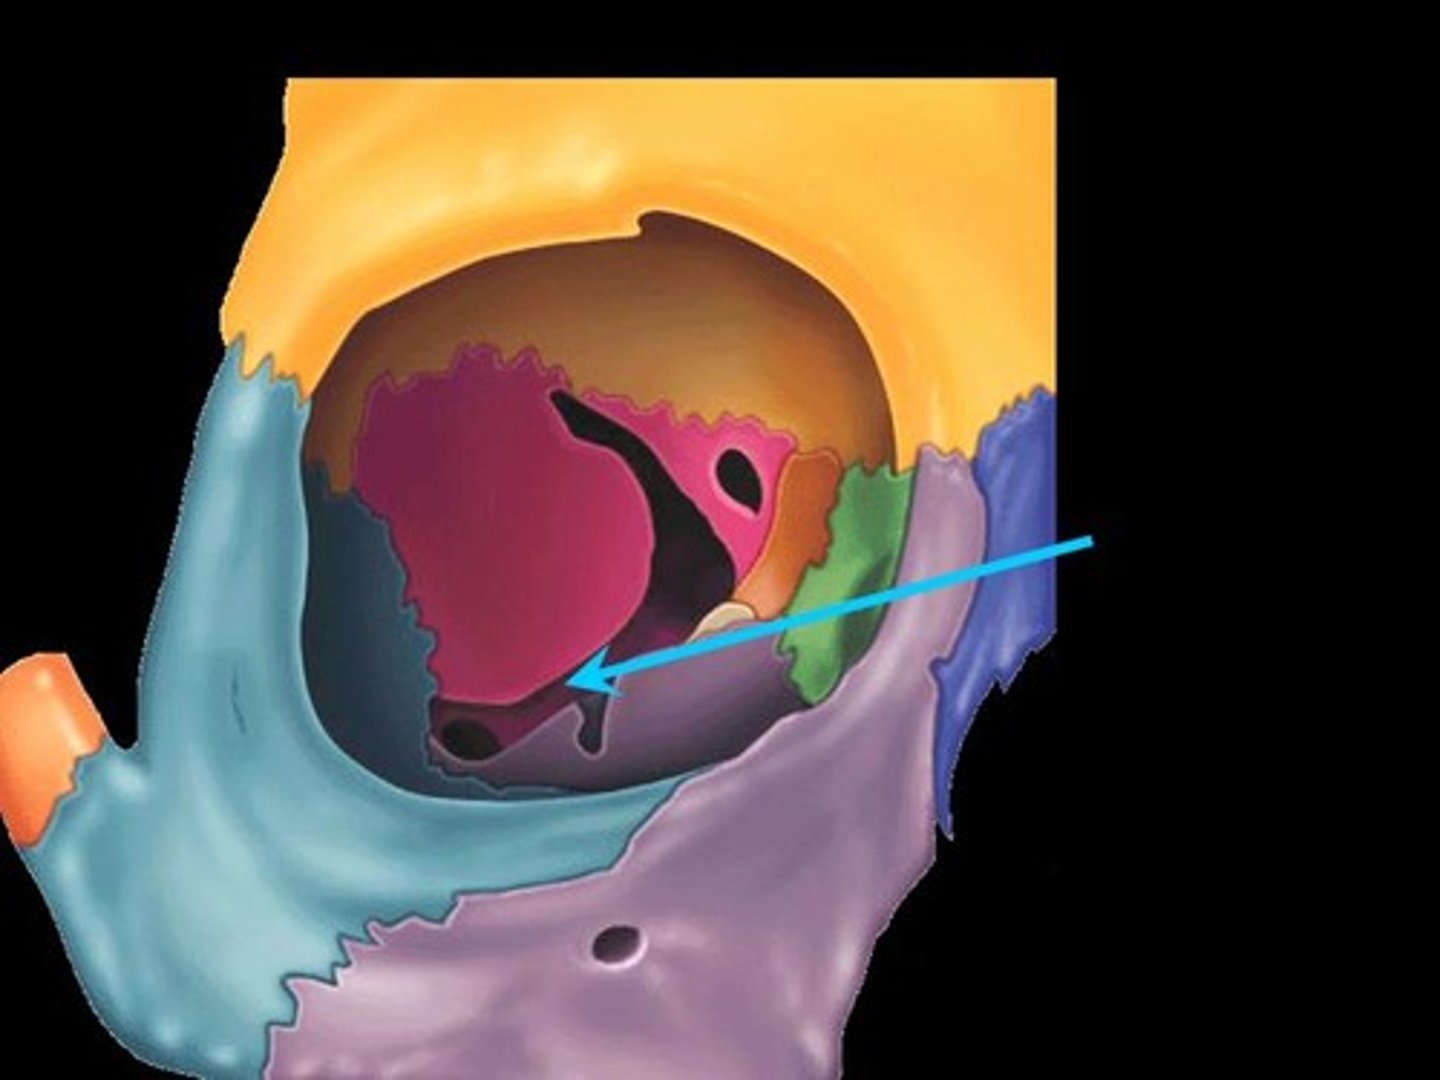

Sphenoid Bone

Forms part of the base of the skull and parts of the floor and sides of the orbit

Superior Orbital Fissure

A foramen in the skull lying between the lesser and greater wings of the sphenoid bone

Inferior Orbital Fissure

An opening in the maxillary bone of the skull located below the infraorbital margin of the orbit. It transmits the infraorbital artery and vein, and the infraorbital nerve, a branch of the maxillary nerve.

Optic Canal

A cylindrical canal running obliquely through the lesser wing of sphenoid bone near the base where it joins the body of sphenoid. It transmits the optic nerve and ophthalmic artery.

Foramen Rotundum

Located at the base of the greater wing of the sphenoid, inferior to the superior orbital fissure. It provides a connection between the middle cranial fossa and the pterygopalatine fossa. The maxillary nerve (branch of the trigeminal nerve, CN V) passes through this foramen.

Foramen Spinosum

The middle meningeal artery, middle meningeal vein, and the meningeal branch of the mandibular nerve pass through the foramen.

Foramen Ovale

An oval shaped opening in the middle cranial fossa located at the posterior base of the greater wing of the sphenoid bone. It transmits the mandibular division of the trigeminal nerve (CN V3) and the accessory meningeal artery.

Sella Turcica

Depression in the sphenoid bone where the pituitary gland is located

Pterygoid Process

Process of the sphenoid bone, consisting of two plates